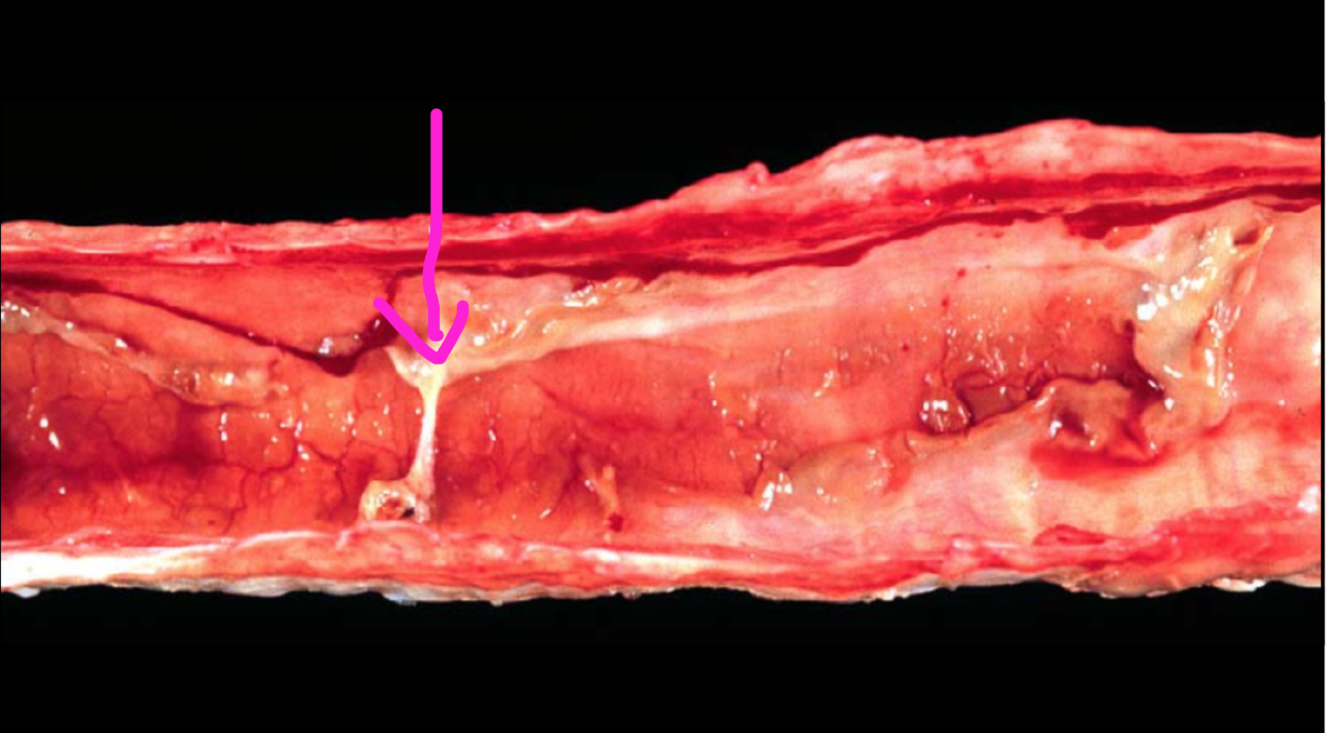

Fibrinonecritic tracheitis

DDX: IBR, MCF

Fibrinonecrotic rhinitis/tracheitis

DDX:

IBR (herpes virus 1)

MCF